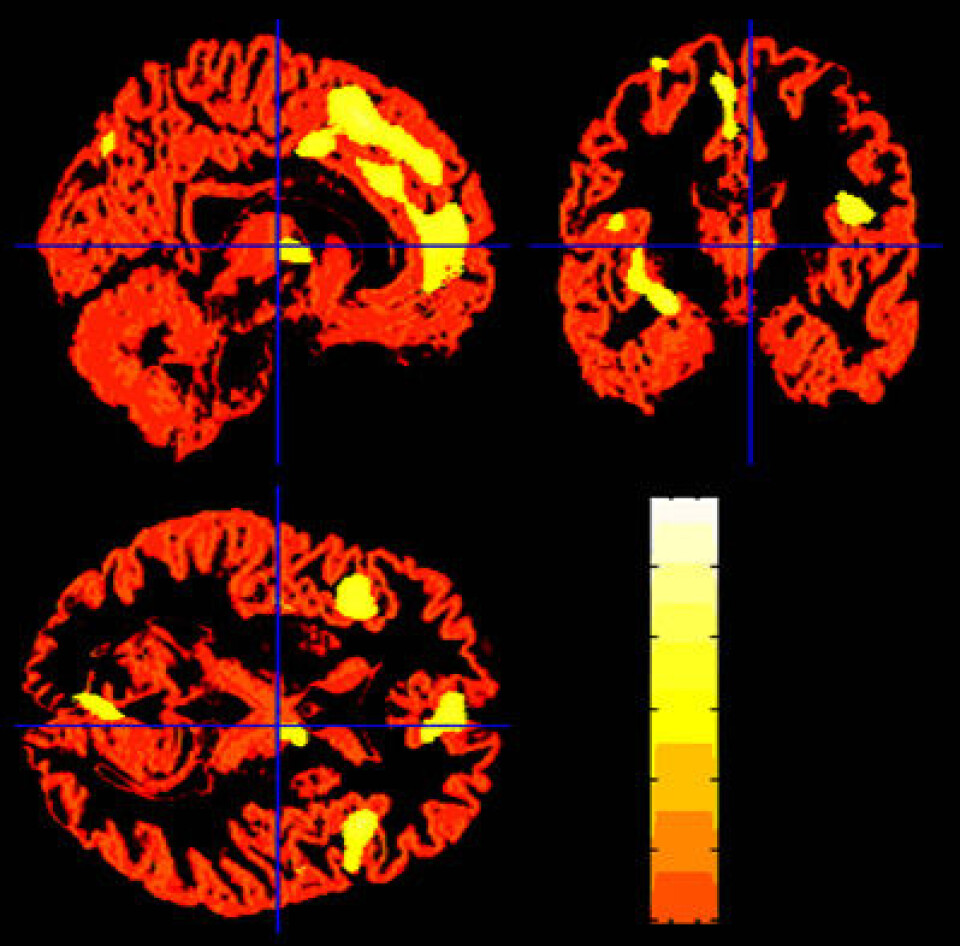

"Hjerneområder som har mindre volum av grå materie, blant de som var i nærheten av terrorangrepet. Alle områdene, som er lyse i fargen på dette bildet, henger sammen med behandling av følelser. (Foto: Barbara Ganzel/Cornell University)"

Resultatene viser at friske voksne mennesker som befant seg i nærheten av World Trade Center under angrepet, har mindre grå materie i viktige følelsessentre i hjernen, sammenlignet med folk som befant seg mer enn 300 kilometer unna.

De som befant seg nær terrorangrepet, hadde mer følelsemessig reaksjon i amygdala, en region i hjernen som fanger opp truende informasjon. Denne hjerneregionen var også mindre.

Dette var igjen knyttet til hvor engstelige personene var flere år senere. Flere andre hjerneregioner som knyttes til behandling av følelser, var også mindre hos de som sto nær katastrofen.